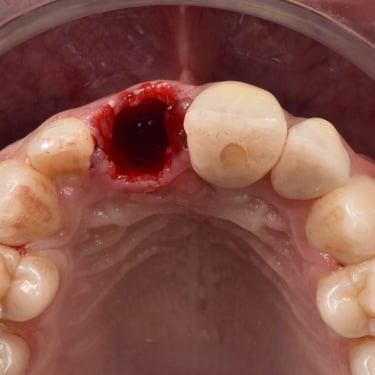

Extracción de Muelas del Juicio

La extracción de las muelas del juicio es un procedimiento quirúrgico para remover los terceros molares que pueden causar dolor, infección o daño a otros dientes debido a su posición o crecimiento anómalo.

Los pacientes pueden experimentar dolor, hinchazón y, en algunos casos, infección alrededor de estas muelas.

El tratamiento incluye la extracción quirúrgica para prevenir o resolver complicaciones.